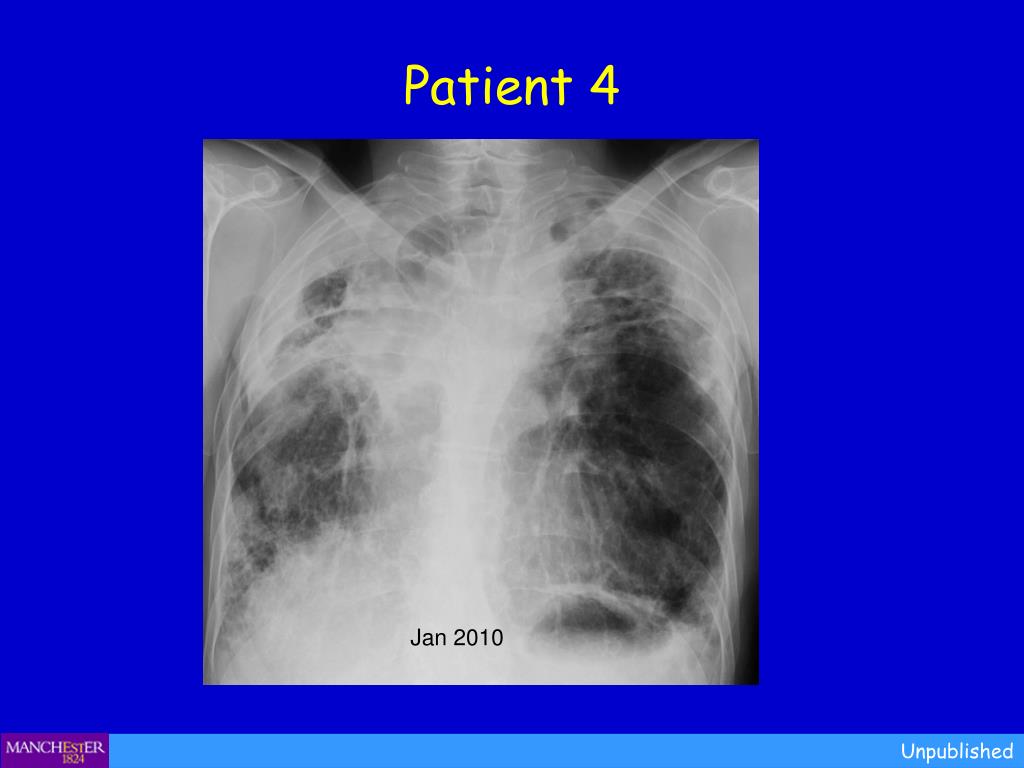

18. Patient 4 • NC (♂, age 73) was commenced on posaconazole 400mg twice daily following progression of CPA despite itraconazole. He had developed CPA following resection of lung cancer. He had had psoriasis for years, with little trouble and almost no treatment. Treatment included salmeterol/fluticasone 25/250mcg 2 puffs twice daily and tiotropium 18mcg daily. Unpublished

19. Patient 4 Jan 2010 Unpublished

20. Patient 4 • NC (♂, age 73) was commenced on posaconazole 400mg twice daily following progression of CPA despite itraconazole. He had developed CPA following resection of lung cancer. He had had psoriasis for years, with little trouble and almost no treatment. Treatment included salmeterol/fluticasone 25/250mcg 2 puffs twice daily and tiotropium 18mcg daily. Random TDM revealed levels of 2.6, mg/l. After 3 weeks of posaconazole he had a remarkable exacerbation of psoriasis. He developed psoriatic plaques on his hands for the first time ever. The plaques on his lower legs became confluent. This occurred in association with worsening chest symptoms, notably increased coughing, more breathlessness and increasing oxygen requirement. Unpublished